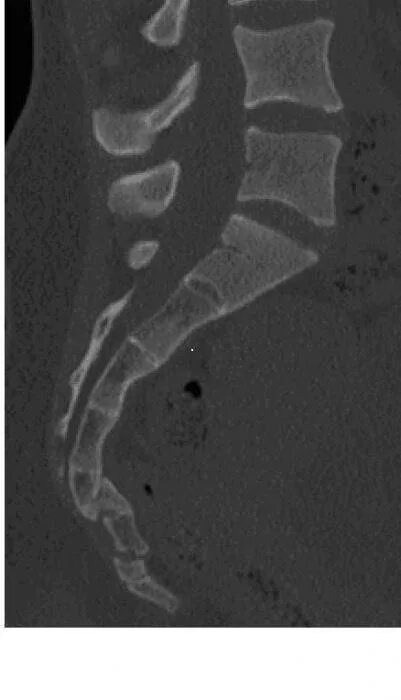

Пояснично-крестцовый отдел позвоночника. хондроз поясничного отдела позвоночника. остеопения поясничного отдела позвоночника. смещение крестца позвоночника.

Отросток l2 позвонка остистый. крестцовый отдел позвоночника крестец. l4 l5 остистый отросток. позвонки крестца кт.

Позвонки пояснично-крестцового отдела позвоночника. пояснично-крестцовый отдел позвоночника строение. поясничный отдел позвоночника анатомия. позвонки крестцового отдела анатомия.

Спондилолистез с4 с5. мрт поясничного отдела спондилолистез. спондилолистез кт. спондилолистез крестца.